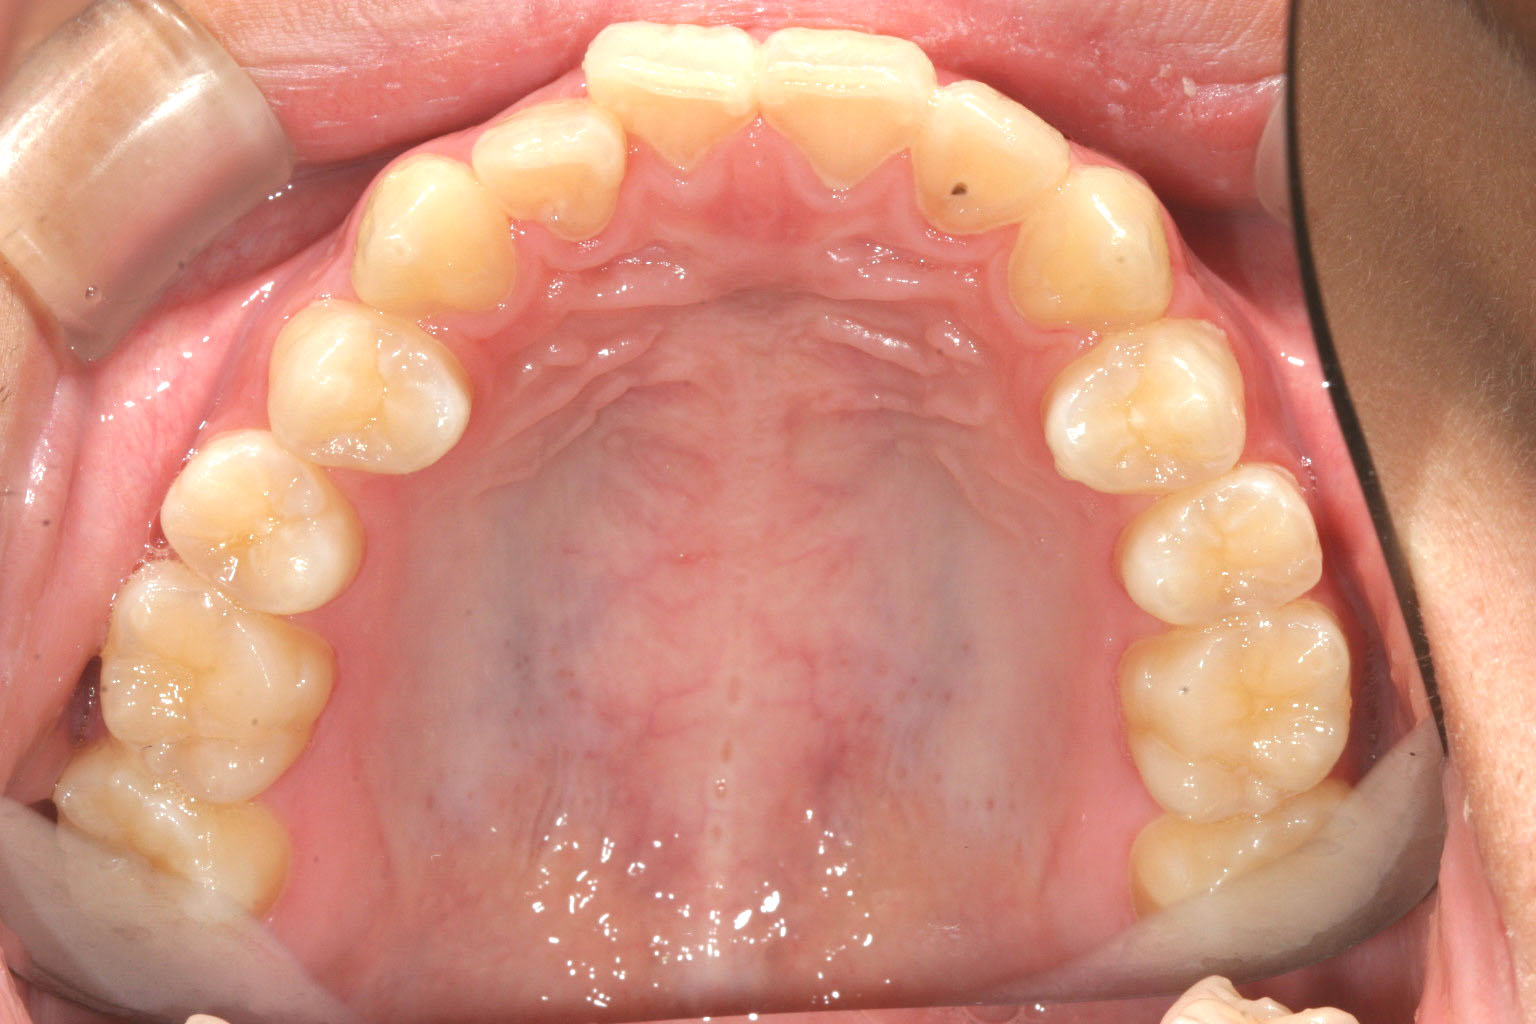

歯列はさほど乱れてませんが少し前歯が出ています。

歯列に問題は無さそうです。

少しアーチが広がりました。